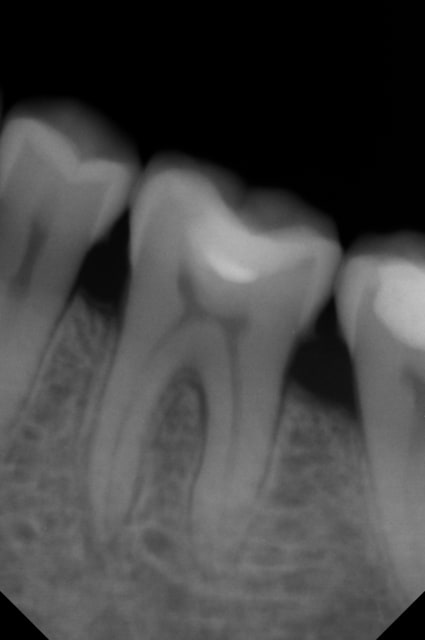

J'ai fait un dépassement relativement important sur cette 36.

Obturation thermafil et sealite. La dent était en état de pulpite et le traitement a été réalisé sous digue ( j'ai fait la radio après l'avoir enlevé)

la radio est très floue.

Néanmoins, il me semble que le dépassement n'est composé que de pâte.. il peut donc y avoir une résorption a long terme.

Moins grave que si ton cône avait débordé..

On ne voit pas le 3 ème canal , peut être qu'une autre incidence pourrait nous permettre d'évaluer son obturation.

Ben quoi elle est jolie cette endo...

Mieux vaut trop long que trop court; surtout que le dépassement semble n'être constitué que de ciment.

Bah quoi elle est parfaite ton obturation, t'as peut être un "puff" de ciment un peu trop gros en distal mais peu importe. Allez couronne moi ça et passe au suivant.